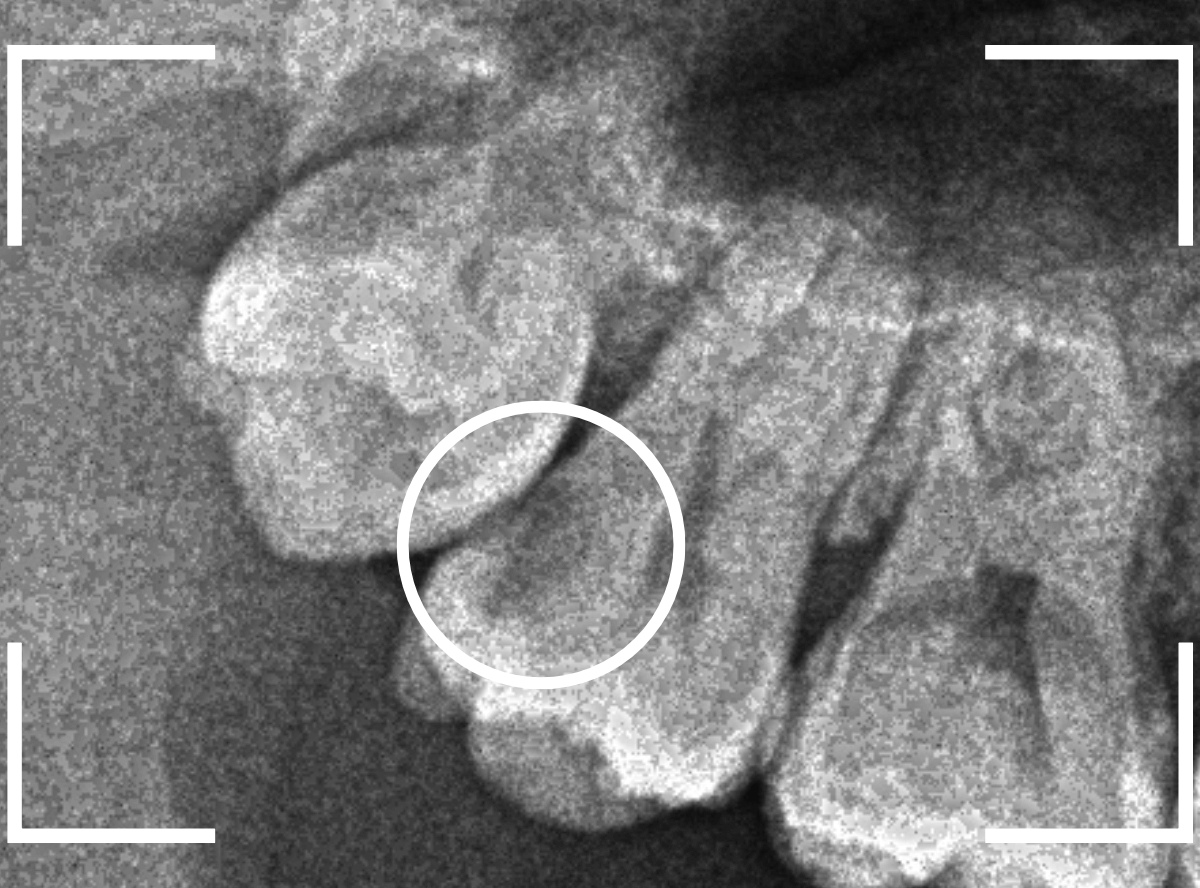

ここでは、比較的簡単なおやしらずの抜歯の例を中心にご紹介します。

このようなおやしらず、あなたはありませんか?